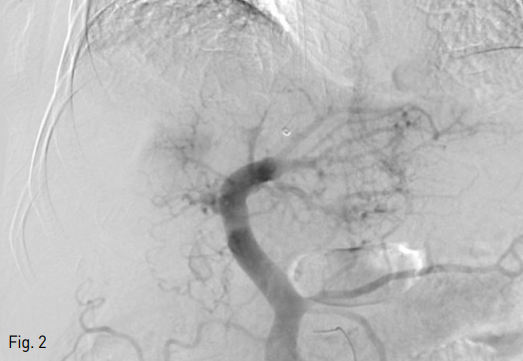

Fig 3A

Oblique axial plane was reconstructed (A) before performing procedure to facilitate sonographic guidance to puncture the left portal vein and left hepatic vein (B).